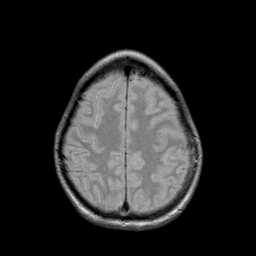

Metastatic bronchogenic carcinoma: proton density-weighted MR -- Slice #18

[Home][Help][Clinical] Slice 18